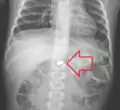

A coin seen on AP CXR in the esophagus -